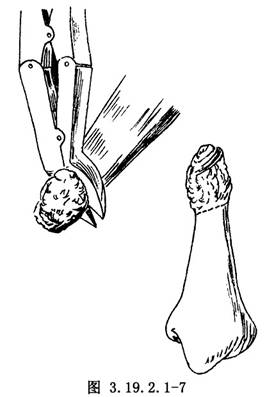

遊離骨端,切除遠、近端硬化的骨組織(圖3.19.2.1-7)。鑽通和擴大遠近端髓腔(圖3.19.2.1-8)。手法矯正脛骨向前成角畸形,並使健康的脛骨遠、近端互相嵌壓。有時需另做切口延長跟腱,以利脛骨成角畸形矯正。如腓骨完整使脛骨兩斷端分離,應另做切口,切除一段腓骨,才能使脛骨兩斷端對正(圖3.19.2.1-9)。以斯氏釘逆行法髓內固定切斷的腓骨(圖3.19.2.1-10)。這樣對脛骨的斷端也提供了良好的對位和固定作用。在手法矯正向前成角畸形時,最好使脛骨矯正到向後成角15°~20°(圖3.19.2.1-11)。